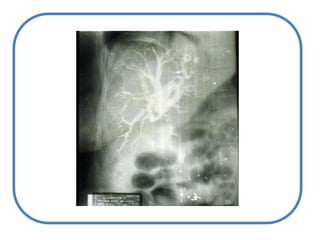

ColestasisIntrahepáticaExtra hepáticaAlteración en el transportadorVías Intra hepáticasHacia el intestinoVías extra hepáticas – pre vesicularesccVesiculares

Anatómica ICTERICIAETIOLOGÍA:CAUSAS POSHEPATICASCAUSAS PREHEPATICASColedocolitiasisAnemia hemolíticaCAUSAS HEPÁTICASCirrosis hepática

Defecto en la excrecionBloqueoparcial o total de la excreción de la  bilirrubina (y sales biliares)

Desde el retículoendoplásmico del hepatocito hasta el duodeno

Litiasis y estenosis de víasbiliares

Tumores: víabiliar, páncreas o encrucijada

Pancreatitis